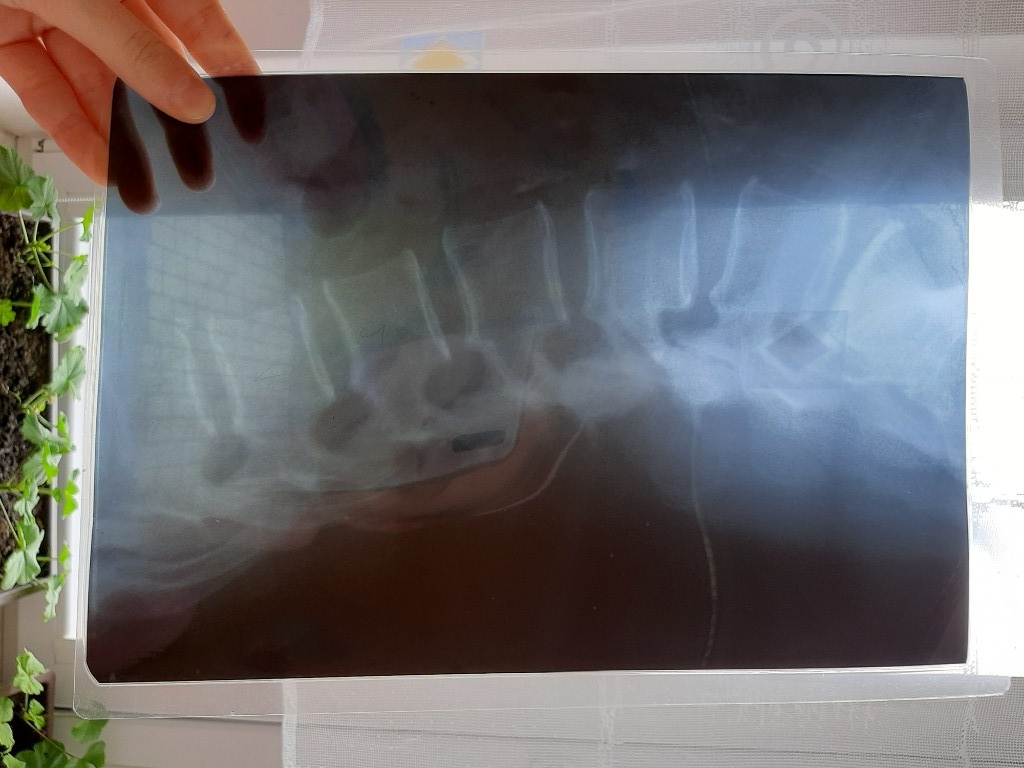

První pomoc v MŠ

Datum: 22. 4. 2022 | Počet fotografií: 279